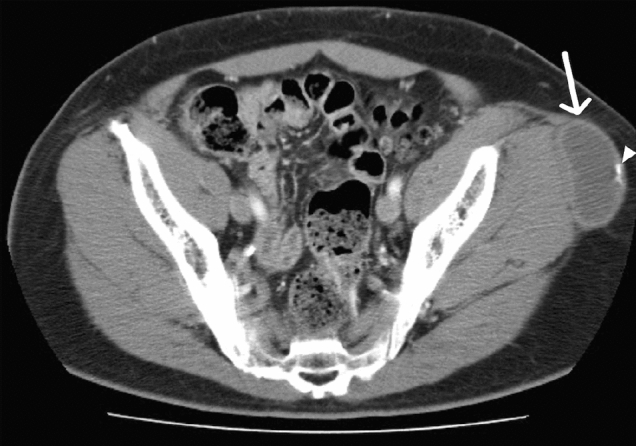

With an incidence of 1 out of 275,000 births, Klippel-Trenaunay-Weber Syndrome (KTS) is a sporadic, rare, congenital syndrome characterized by port-wine stain (nevus flammeus), vascular malformations (varicosities and hemangiomas), asymmetric appendicular bone, and soft tissue hypertrophy. Only two of the three criteria need to be present to make a diagnosis KTS. The involvement of the gastrointestinal and genitourinary systems is not uncommon. Routine CT can detect enlargement of the extremity with bone elongation and circumferential soft tissue hypertrophy, subcutaneous varicose veins, phleboliths, and capillary malformation suggesting the diagnosis (Fig. 24). MRI and MR angiography (MRA) are beneficial to evaluate vascular malformation preoperatively [50].

Fig. 24.

30-year-old male with Klippel-Trenaunay-Weber Syndrome. Axial mid-abdomen CT (a) images demonstrate enlargement of the subcutaneous tissue of the right flank (arrow) and large splenic hemangioma (arrowhead). Axial pelvic CT (b) images show mesenteric venous malformations associated with phleboliths (arrowhead) and colonic hemangiomatosis with phleboliths (arrow). Coronal posterior abdomen CT (c) images show splenic and mesenteric hemangiomas with associated calcifications (arrow). Axial upper thigh CT (d) images demonstrate gigantism of the right lower extremity with soft tissue hypertrophy and numerous subcutaneous varicose veins (arrow)